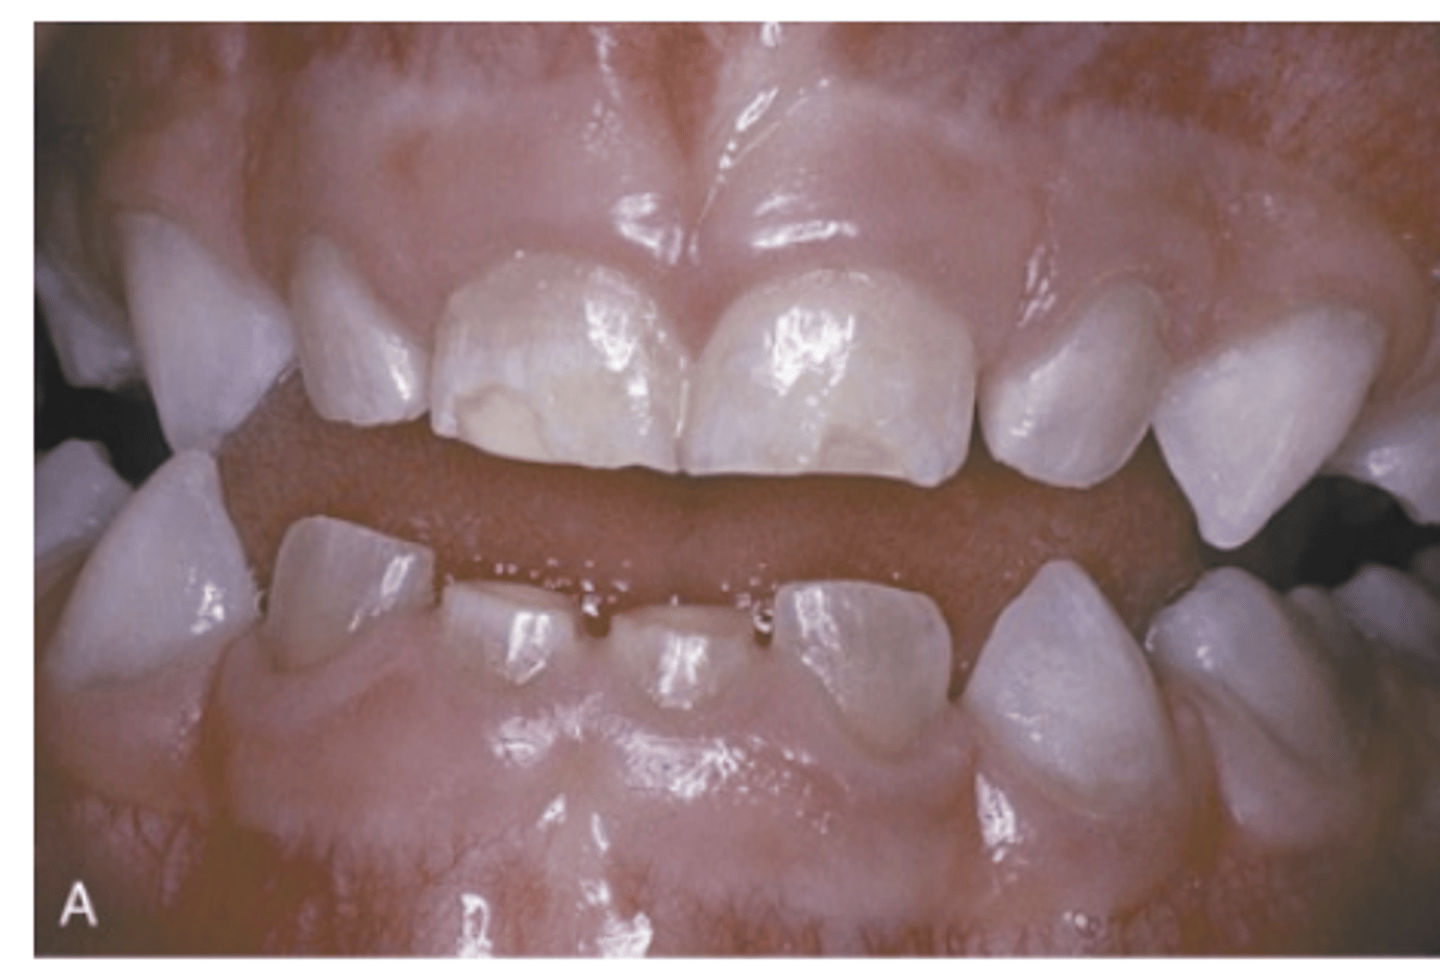

In which types of Osteogenesis Imperfecta are dental alterations more evident?

Types III and IV

What do dentinal defects in Osteogenesis Imperfecta lead to?

Attrition, loss of vertical dimension, and potential tooth loss.

What type of malocclusion is more prevalent in Osteogenesis Imperfecta?

Class III malocclusion.